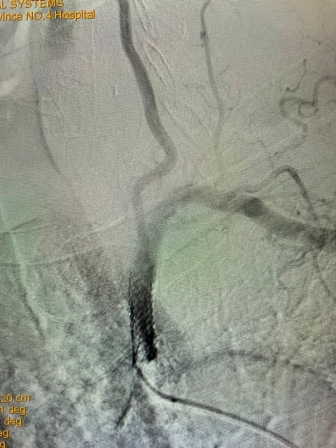

2021年8月5日,我院神经内科神经介入专家团队成功完成首例锁骨下动脉再通介入术

(术前造影) (术后再通造影)